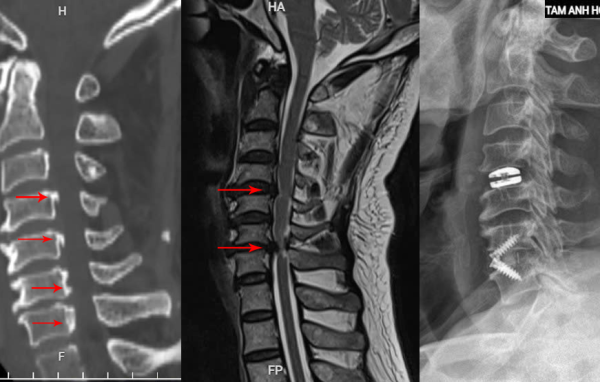

Thoát vị đĩa đệm cổ: Nguyên nhân yếu liệt tay chân & cách điều trị

Trong suốt ba năm, ông Thức phải đối mặt với tình trạng yếu dần ở tứ chi, dù đã thử nhiều phương pháp điều trị như thuốc nam và các loại thực phẩm chức năng nhưng không cải thiện. Gần đây, tình trạng của ông trở nên nghiêm trọng hơn với các triệu chứng nóng…